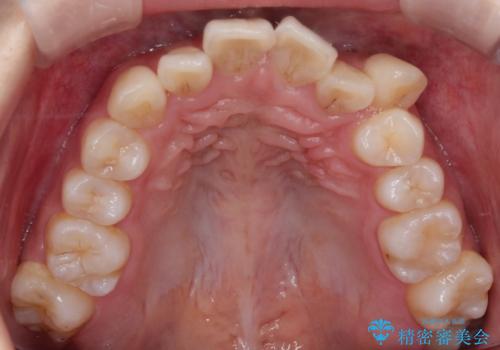

- 八重歯(叢生)と、上下の歯の中心線(正中)がずれていることを主訴にご来院されました。精密な検査の結果、歯列全体のスペースが大幅に不足しており、八重歯を正しい位置に配列し、正中のズレを改善するためには、上下左右の第一小臼歯を抜歯する必要があると診断。装置には、目立ちにくい審美ワイヤーを使用し、見た目を気にせず、機能性と審美性が完璧に整った咬み合わせを目指す治療計画を立案しました。

八重歯: 突出していた八重歯を歯列内に誘導し、デコボコを解消しました。

治療の結果、長年気にされていた八重歯と正中のズレが解消し、機能的にも整った理想的な歯並びを獲得。目立たない装置で治療を完遂し、自信を持って笑える美しい笑顔を手に入れていただけました。